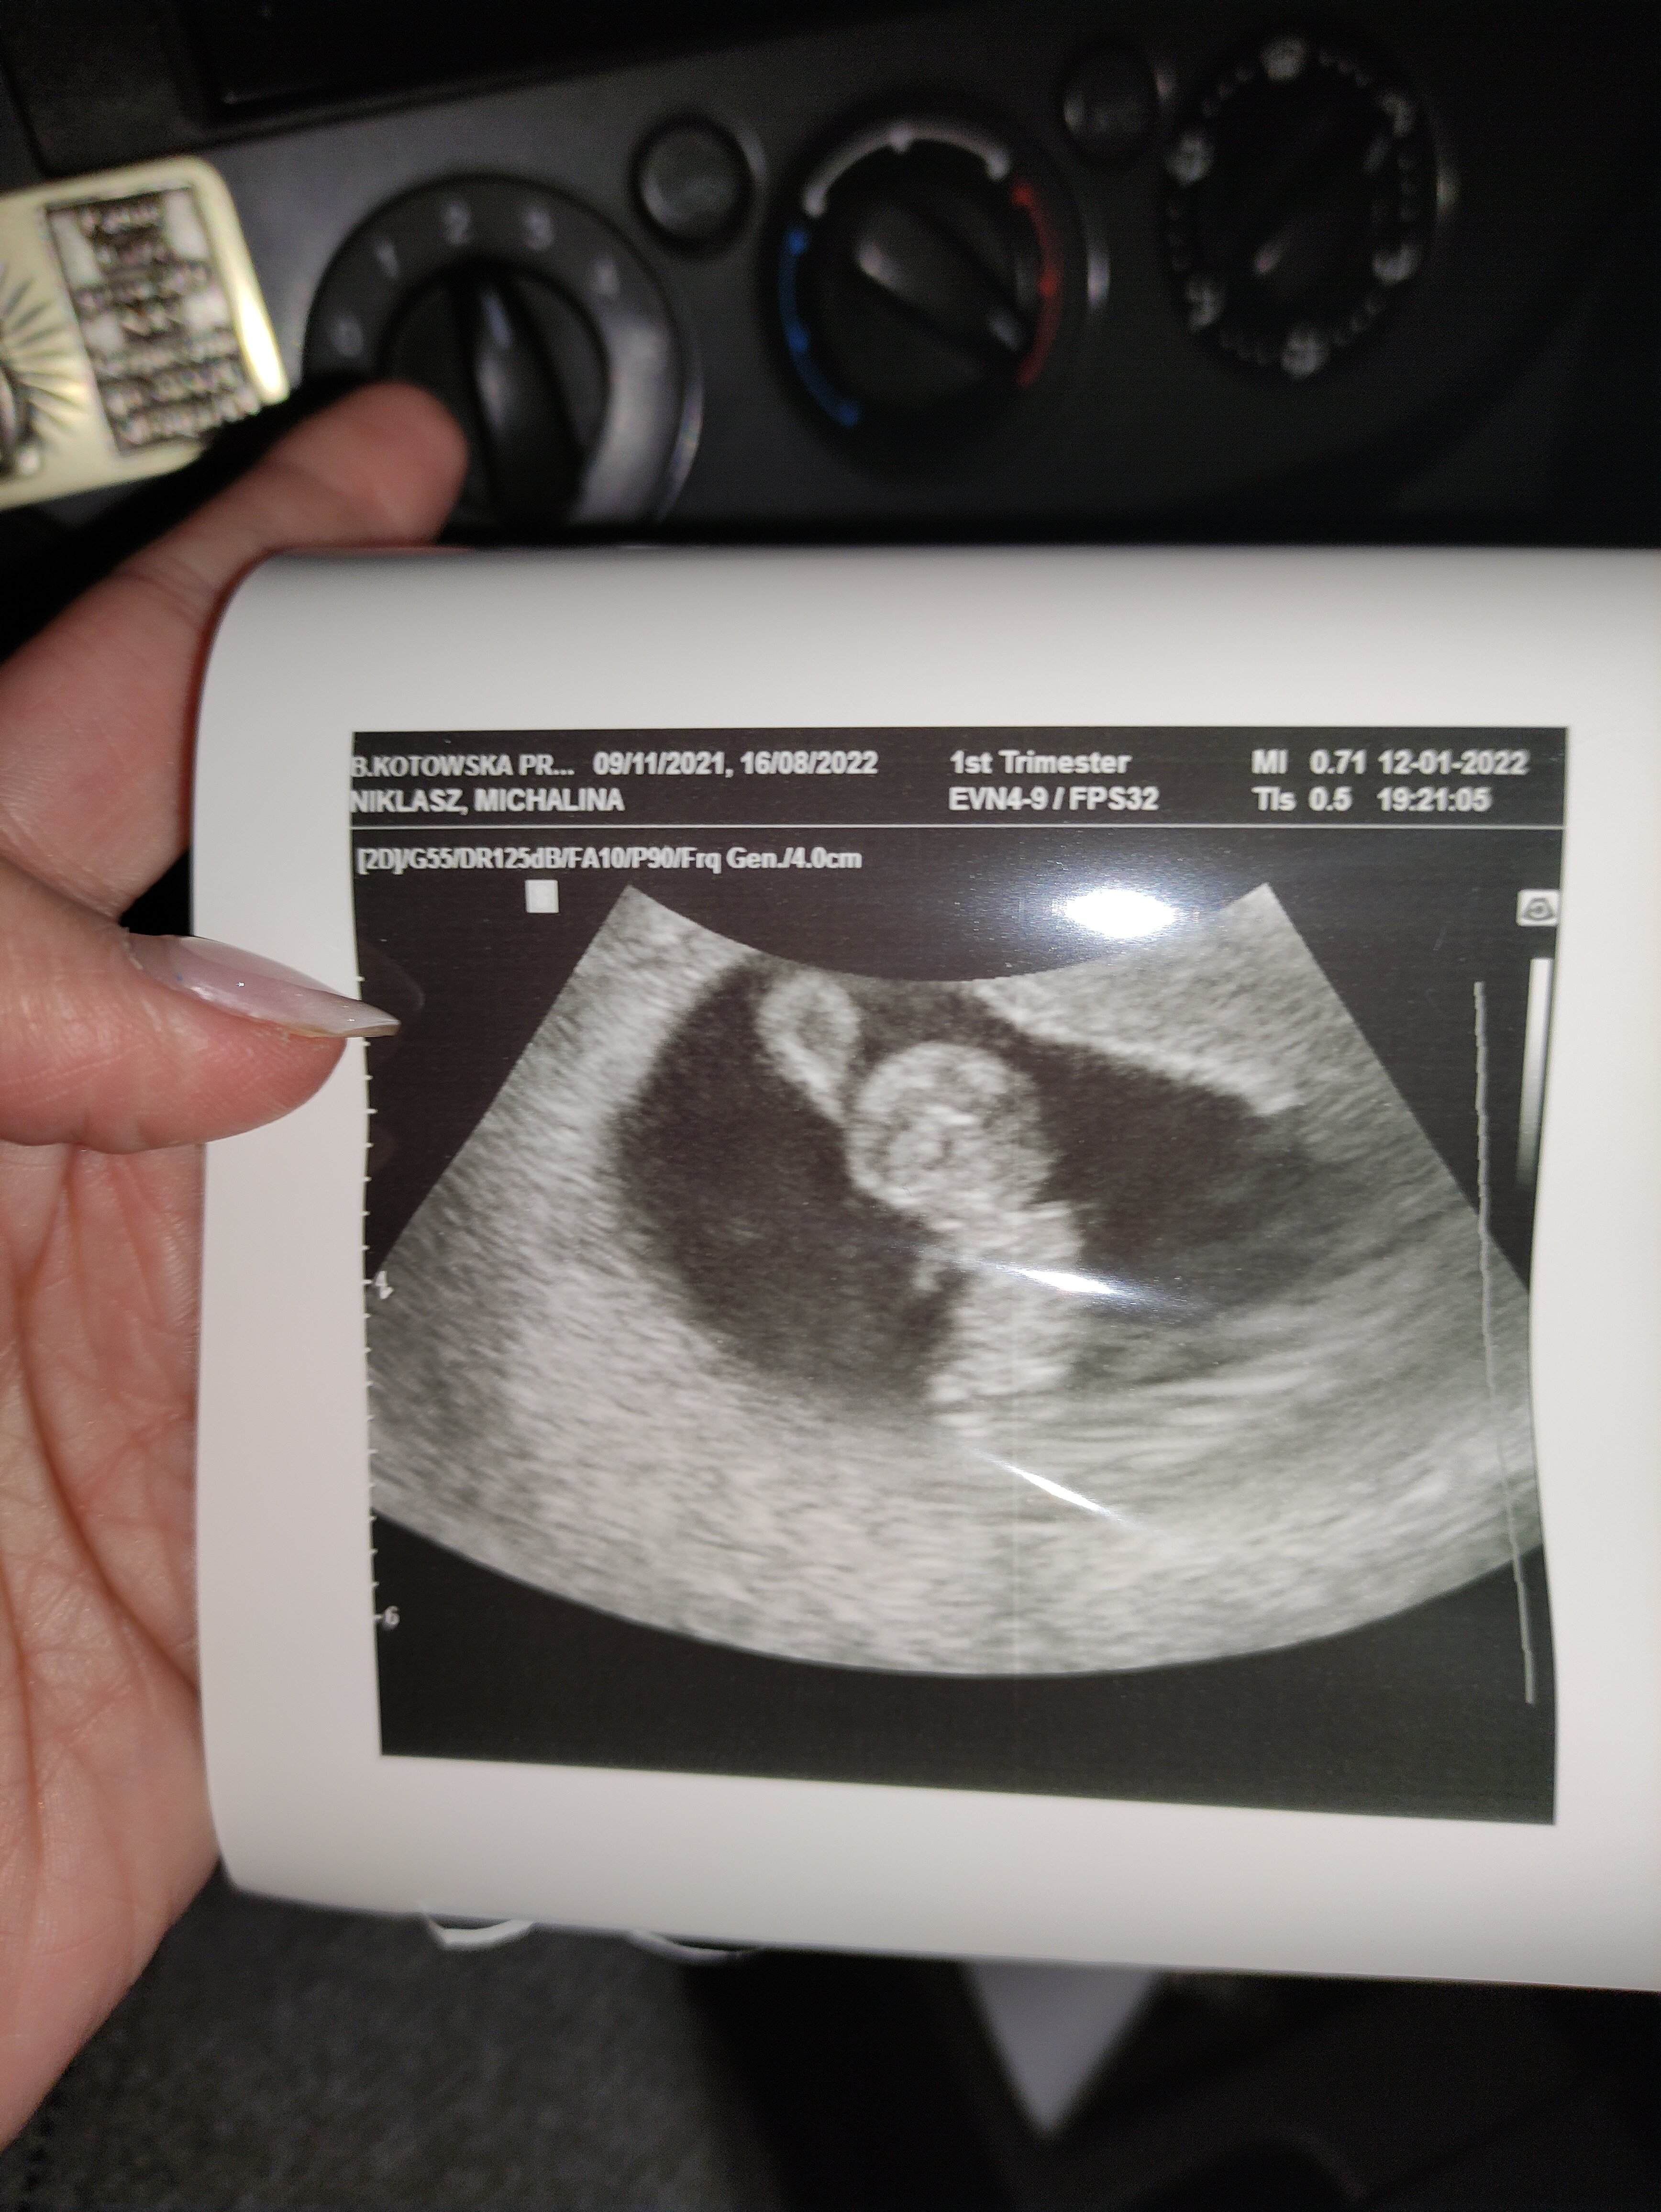

Mam w tej chwili podobną sytuację. Tylko u mnie zarodek był, ale na kolejnym USG brak zarodka i wielki krwiak (ginekolog mówił, że mógł się ukryć). Niestety krwiak spłaszczył pęcherzyk :(

U mnie to wygląda trochę gorzej. Te czarne pole obok pęcherzyka to wielgachny krwiak. Ginekolog mówił, że będzie się teraz złuszczał i nic się nie dzieje...

Załączniki

• IMG_20220109_165111.jpg

IMG_20220109_165111.jpg

944 KB · Wyświetleń: 127